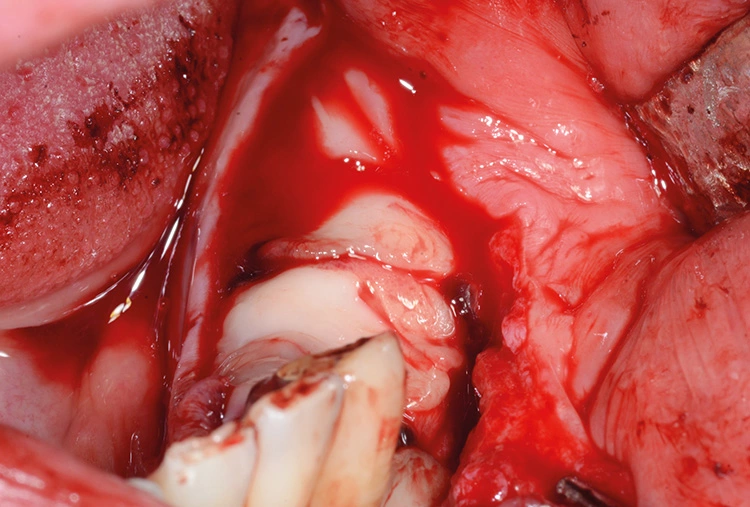

Implantation: 7 Monate nach Augmentation

Trotz der schlechten, hart- und weichgewebigen Grundvoraussetzungen konnte der Kieferkamm zufriedenstellend rekonstruiert werden. Die Augmentation des kombinierten, horizontalen und vertikalen Defekts mit Yxoss CBR®, Geistlich Bio-Oss®, Geistlich Bio-Gide®, autologem Knochen und PRF ermöglichte die Implantation mit hoher Primärstabilität in den rekonstruierten Bereich.